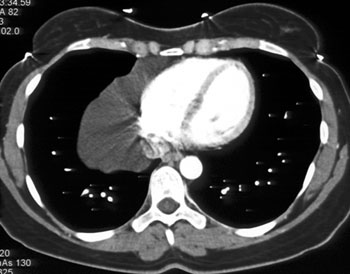

Over half of pulmonary artery sarcomas are misdiagnosed as chronic pulmonary thromboembolism based on their almost identical radiographic findings . Furthermore, the usual presenting symptoms of pulmonary artery sarcoma are dyspnea, chest pain, cough or hemoptysis, which also make the lesion clinically indistinguishable from pulmonary thromboembolism. With difficult clinical and radiographic diagnosis, the tumors are often incorrectly managed and ultimately diagnosed upon surgical treatment for presumed thromboembolic disease . References: - Mandelstamm M (1923) Ueber Primaeren Neubildungen des Herzen. Virchow Arch Path Anat 245: 43-54.

Here is a case that was a true saddle pulmonary embolism. Note some of the key differences between the two cases are that the tumor fills in the entire vessel with no wall seen.

Saddle pulmonary embolism |